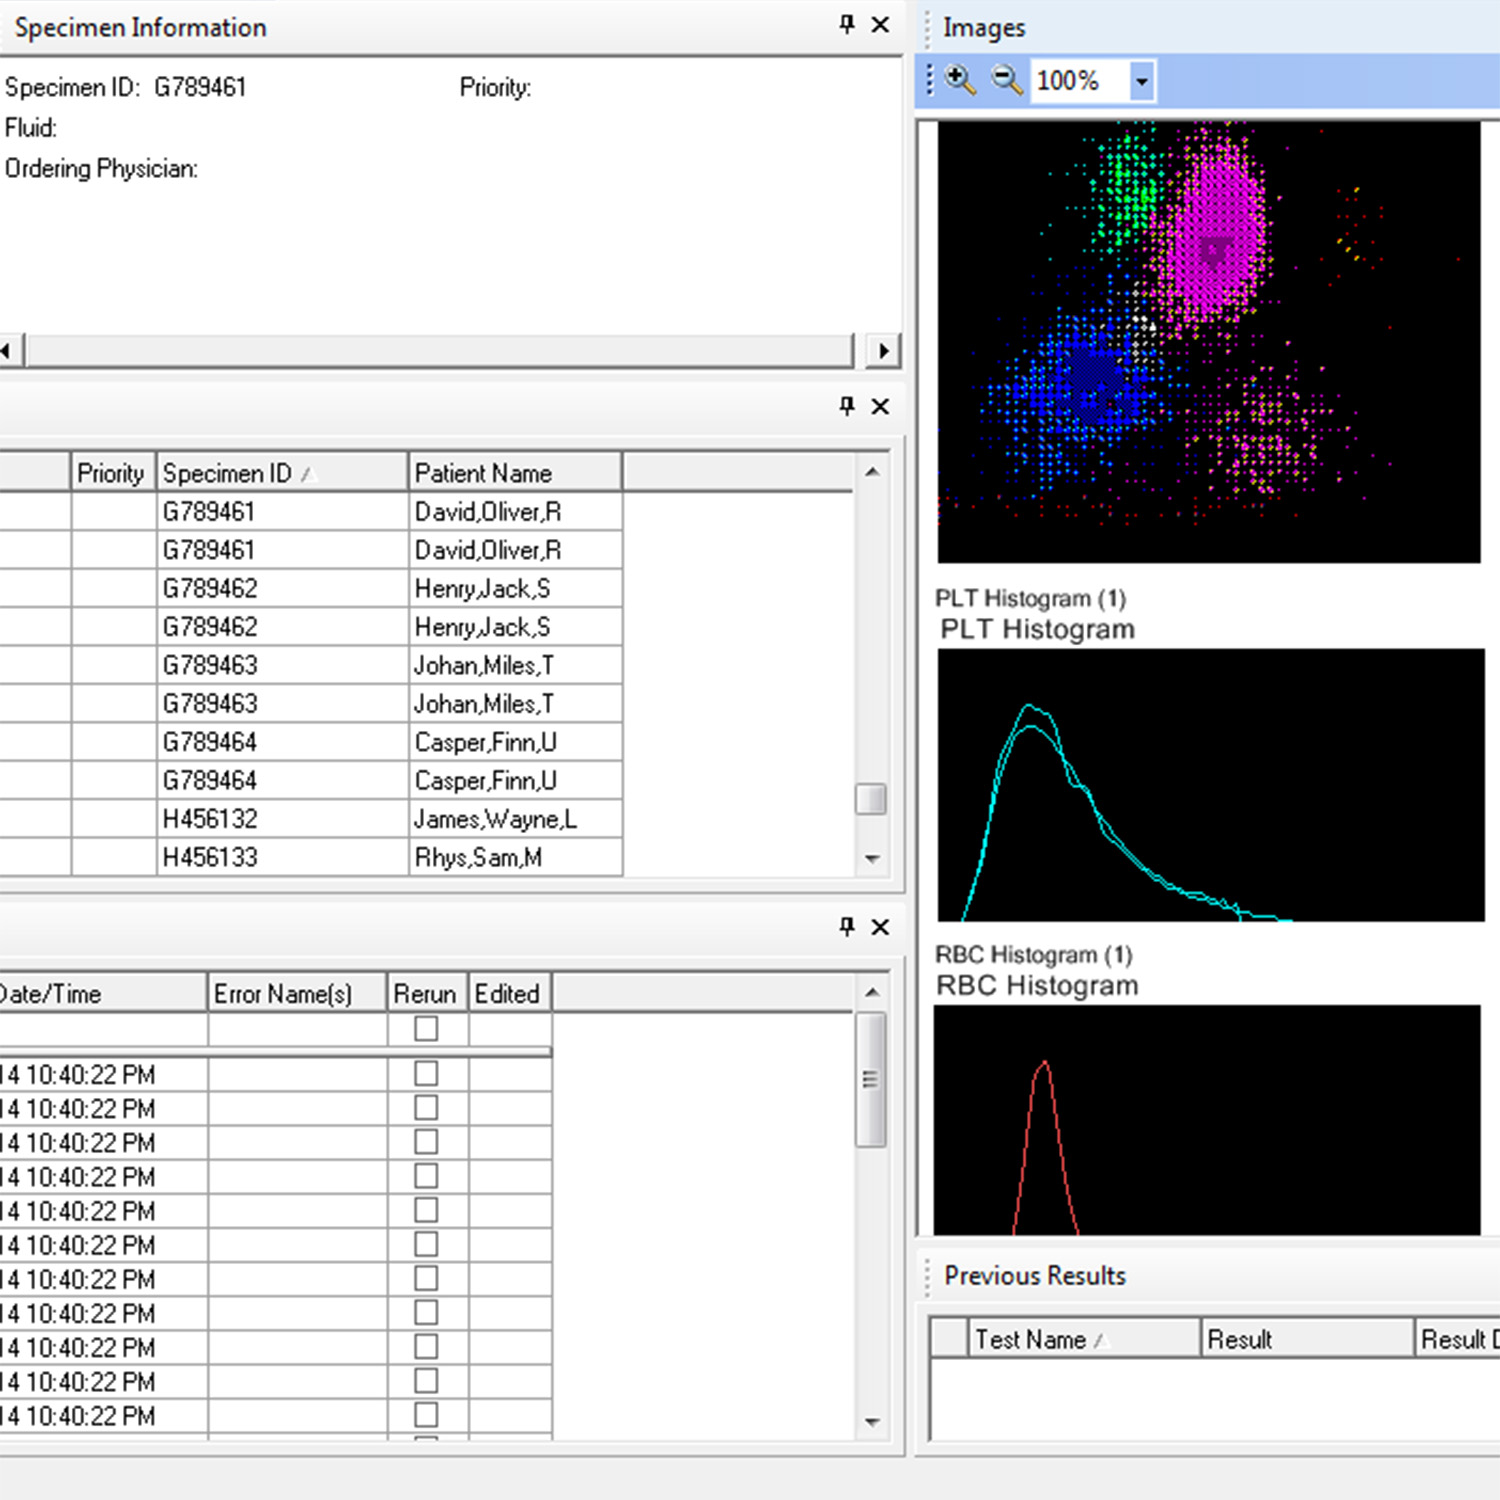

Specimen Management Workspace

The comprehensive Specimen Management workspace enables improved patient care with customizable displays for tracking and reporting results.

- Sort by discipline, instrument, or other metric.

- Color code STAT and high-priority results for escalated review.

- View patient demographics with test results to assist with decision-making.